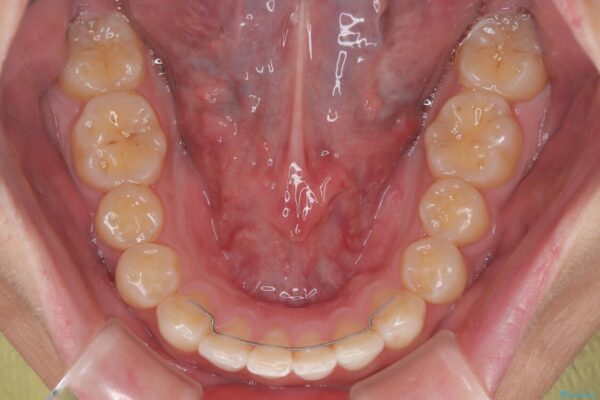

治療後

• 前歯のガタガタ・奥歯のかみ合わせ(シザーズバイト)を改善|1年半で完了したメタルブラケット矯正 治療後画像